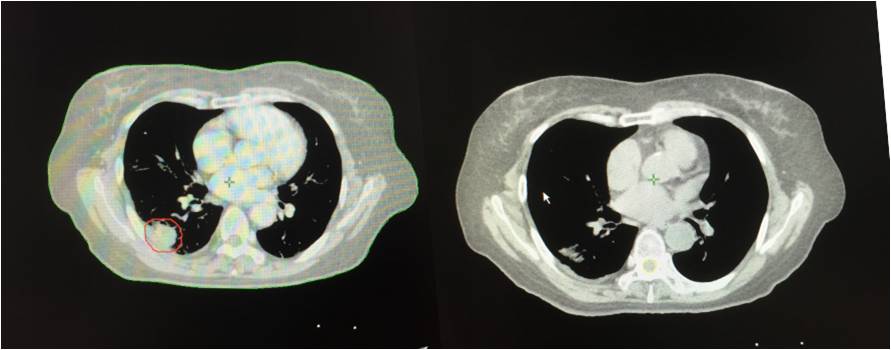

A45治疗肺腺癌患者案例

患者周女士,65岁,肺腺癌。

2013年3月初无明显诱因出现胸闷、气短,活动时加重,伴有间断左侧肩胛区疼痛,无咳嗽、咳痰,无发热、咯血,无盗汗、乏力。2013年4月胸部CT示:右肺占位。4月末在北京大学人民医院行胸部CT增强示:双肺下叶背段恶性病变,考虑肺癌可能性大。5月在*警武**北京总队第二医院行PET/CT检查提示:1.双肺下叶背段斜裂胸膜下高代谢结节,考虑恶性病变,肺癌可能大,双肺多发磨玻璃结节及微小结节,未见明显高代谢,倾向恶性病变;2.右乳外下象限小结节伴代谢,结合临床。

2013年5月入院,肺穿刺病理结果提示:左下肺腺癌。

2013年5月、6月接受四次A45肿瘤治疗治疗四次。2013年10月再次接受全身A45肿瘤治疗1次,右下肺病灶A45肿瘤治疗1次,出院后继续口服易瑞沙靶向治疗。患者肿瘤缩小,几乎消失。患者的状态稳定。

治疗前 治疗后